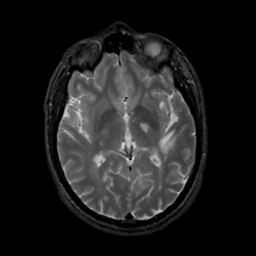

MR Study #1, February 10, 1991 -- Slice #25